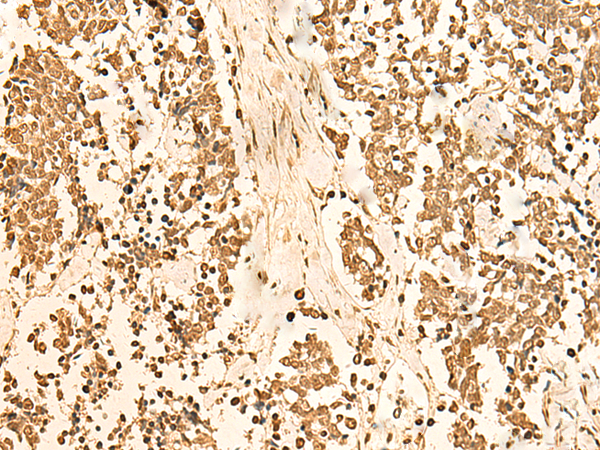

IHC positive control:

Human breast cancer and Human lung cancer

IHC Recommend dilution:

50-300